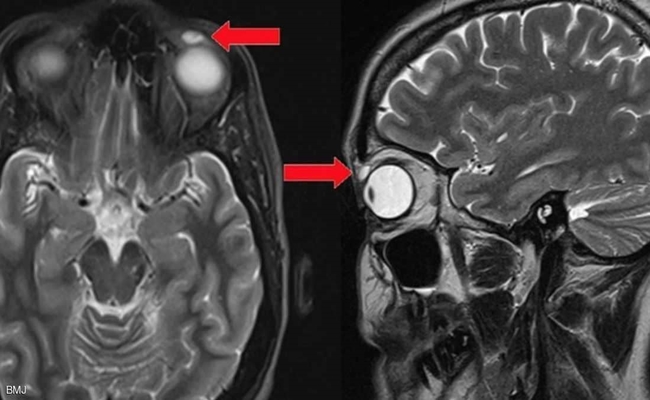

وأظهر فحص بالأشعة أن المشكلة الصحية ناجمة عن وجود عدسة يناهز حجمها 8 ميليمترات، وهو ما جعل الطبيب يلجأ إلى الجراحة لإزالة العدسة التي ظلت في مكانها قرابة ثلاثة عقود.